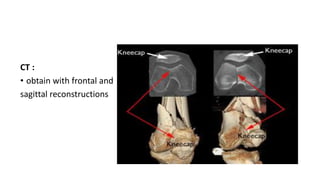

CT :

• obtain with frontal and

sagittal reconstructions